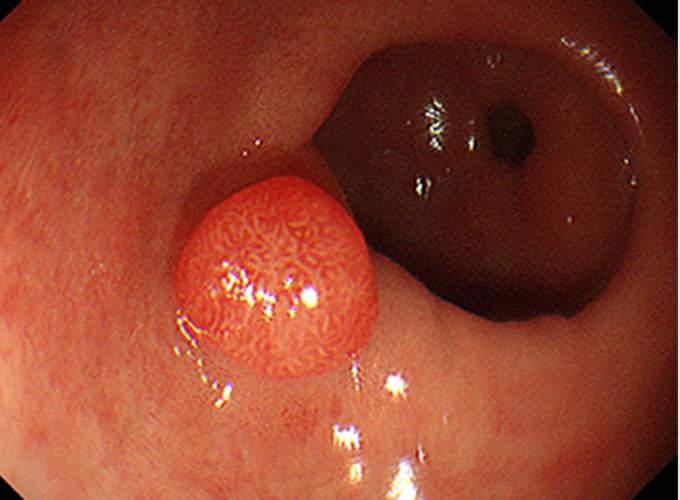

狭帯域光観察:NBI(Narrow Band Imaging)BLI(Blue LASER Imaging)

このシステムでは、狭帯域化された2つの波長の光を用いることにより、発見が困難な病変を見つけたり、がんの範囲の詳細な診断をすることが可能です。 特に、食道がんや咽頭、喉頭のがんはNBIで観察することで、発見の精度が上がります。

下部消化管内(大腸カメラ)視鏡検査の検査と治療

下部消化管(大腸カメラ)内視鏡検査では、肛門より太さ約13~14mmの内視鏡スコープを挿入し、空気(炭酸ガス)の注入を行いながら大腸のヒダをたぐり寄せて盲腸まで挿入します。 盲腸へ到達後、ポリープやがん、炎症などの病気がないか観察しながら内視鏡スコープを抜いてきます。 途中で病変が見つかった場合は、必要に応じて病変の一部を採取(生検)して調べたり、ポリープや早期がんなどの病変を内視鏡的に切除することもできます。検査時間は通常10~15分程度ですが、ポリープを切除すると通常より時間は長くかかります。

大腸ポリープまたは早期大腸がんの内視鏡治療

良性のポリープや早期がんの中でも粘膜だけにとどまっているもの、粘膜下層へわずかに広がっているものが内視鏡治療の適応となります。 小さなポリープに対しては、鉗子でつかみながら高周波電流を用いて病変の根もとを焼き切ります(ホットバイオプシー)。 茎のあるポリープに対しては、輪の形のスネアを茎の部分でしめ、高周波電流を用いて切断します(ポリペクトミー)。 茎のない病変に対しては、内視鏡的粘膜切除術(EMR)や内視鏡的粘膜下層剥離術(ESD)などを行います。